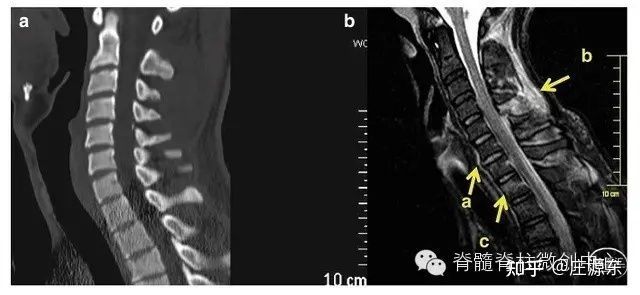

为目前已知的最好的建立临床 - 影像学相关性的方法,对于急性脊髓创伤术前的入路计划和提高疗效至关重要(图 1,图 2)。

图 2 CT(a) 和 MRI(b) 在韧带损伤和骨组织水肿方面的比较,只有 MRI 能看到,T2 加权高信号。MRI 中 a 为前纵韧带损伤,c 为骨组织水肿,b 为后方韧带复合体损伤。